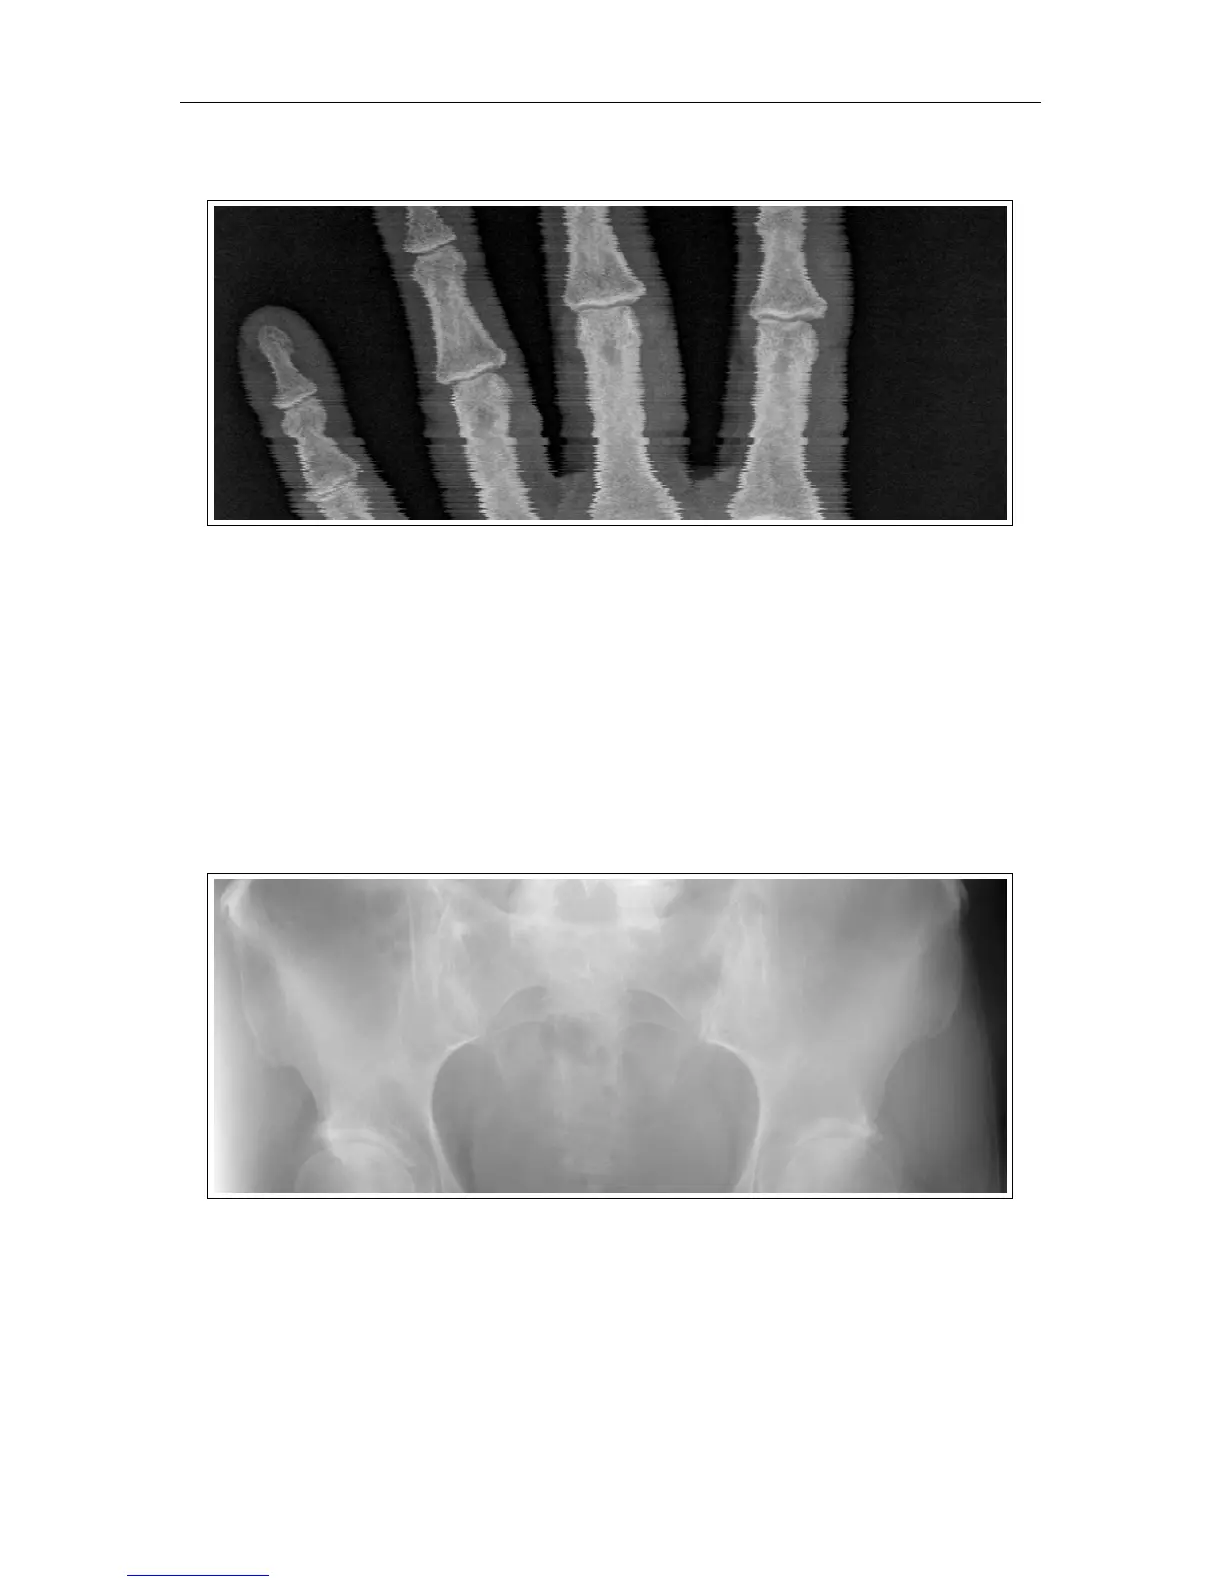

7.3.8 Image Jitter

Symptom: Jittery image.

Cause: Inconsistency in the CR unit’s galvanometer.

Solution: Image jitter issues are

not

serviceable in the field. Please contact Technical

Support for assistance with image jitter.

7.3.9 Over Exposure

Symptom: Lines in images / images look more “translucent”– the images lack the proper

contrast and density.

Cause: Over exposure.